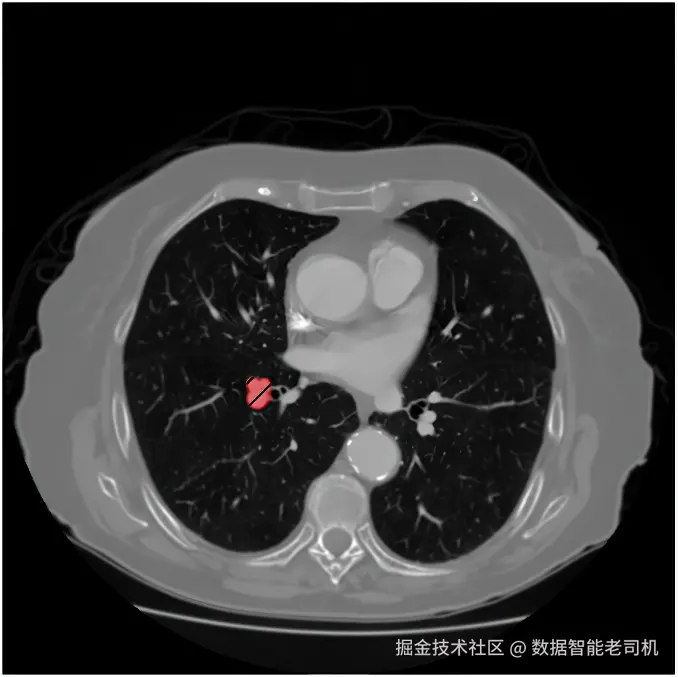

image.png

图 15.10 带有结节分割 mask 的肺部 CT 扫描切片